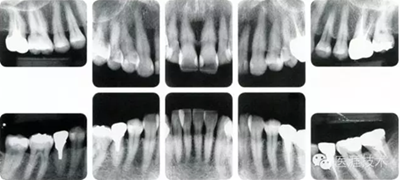

圖為50歲女性,無特殊全身疾病,不抽煙。持續(xù)保養(yǎng)6年。無填充物等問題,依照患者本人要求持續(xù)觀察。牙周組織臉頰側(cè)雖見部分萎縮,但X線牙片顯示牙間無骨吸收現(xiàn)象,保持著比較健康的狀態(tài)。